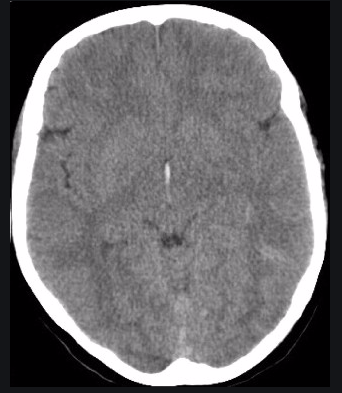

How can you tell if a subdural haemorraghe visible on CT is chronic or acute?

- Less midline shift if chronic so neurological abnomalities may not be present